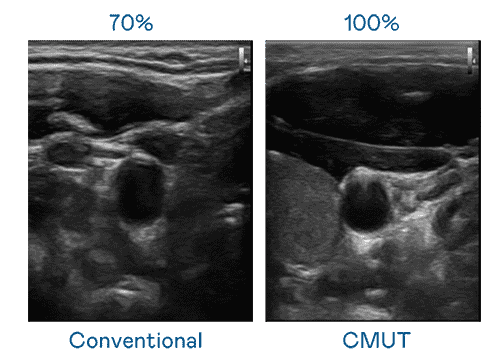

CMUT 技术是一种用电容式微机电元件来产生超音波讯号的技术。。。。与传统 PZT 压电式技术相比,,,CMUT 频宽增加 30%,,,更宽频的超音波讯号让影像解析度大幅提升,,是实现高影像品质医疗超音波扫描、、、、促进精准医疗发展的关键技术。。。。

大频宽带来超清晰影像

超音波影像的解析度高低,,,首先取决于探头能发出的讯号频宽。。。尊龙集团 CMUT 可提供高清晰的超音波讯号,,,,提供高频宽、、高灵敏度、、、影像纹理细节更高的超音波影像,,,,协助医护人员缩短影像判读时间及利用精准的医疗影像进行诊断。。